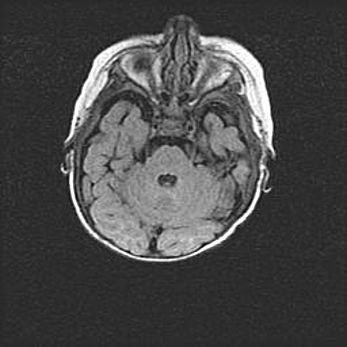

Церебральная ишемия II.

Возраст: 5 дней

Вес: 3400 г

Пол: женский

Окружность головы: 35 см

Срок гестации: 39 недель

Церебральная ишемия – это заболевание, характеризующееся недостаточностью (гипоксией) либо полным прекращением (аноксией) снабжения мозга кислородом по причине закупорки одного или нескольких сосудов. Это приводит к  что метаболическим расстройствам различной степени тяжести в тканях головного мозга, развитию коагуляционных некрозов и гибели нейронов.